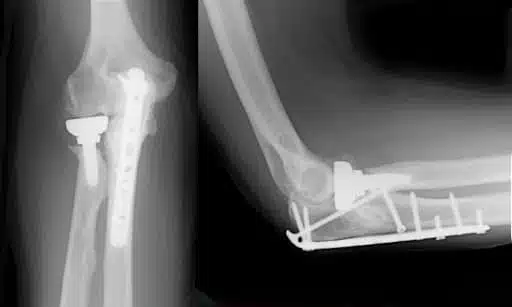

Elbow Plate and Screw Installation Procedure, Are you experiencing pain, disability, and an inability to perform your daily tasks due...